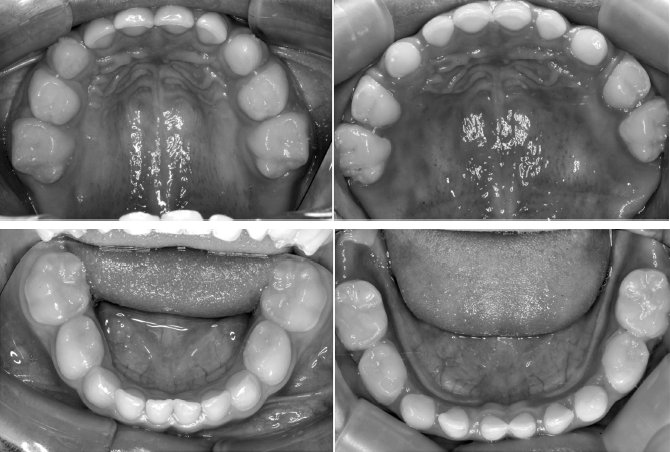

Рисунок 69. У этой четырехлетней девочки между молочными зубами не было промежутков. Чтобы ей было легче дышать, она поднимала подбородок. Она прошла шесть месяцев терапии по расширению челюсти и выработке правильной осанки лица, и полученный результат наглядно демонстрирует, как важно начать лечение в раннем возрасте (фотографии любезно предоставлены доктором Саймоном Вонгом)

Рисунок 70. Чтобы коренные зубы выросли ровными, без скученности, между молочными должны быть промежутки. Обратите внимание на изменения после шести месяцев терапии по расширению челюсти и выработке правильной осанки. Только посмотрите, как комфортно языку на фото справа!